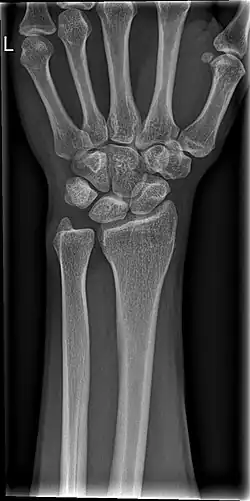

De pols of carpus is het gewricht dat de hand met de arm verbindt.

De pols is een tweeassig eivormig gewricht, wat betekent dat het eigenlijk uit twee gewrichten bestaat. Enerzijds maakt de pols palmair- en dorsaalflexie mogelijk, en anderzijds radiaal- en ulnairabductie. Palmair is de buiging richting de handpalm, dorsaalflexie is de strekking richting de rug. Radiaalabductie is een beweging van de duim naar de pols, ulnairabductie een beweging van de pink naar de pols.